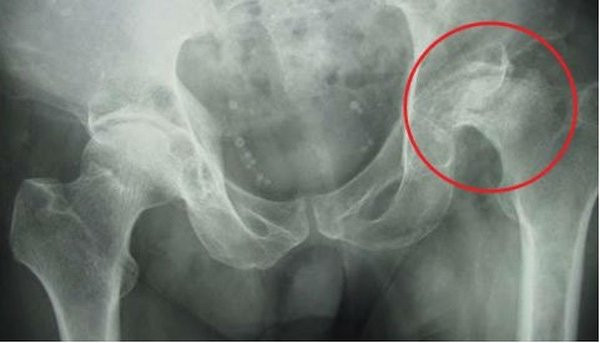

Kết quả chụp cộng hưởng từ (MRI) cho thấy người bệnh bị hoại tử chỏm xương đùi hai bên và buộc phải thay khớp vì không thể điều trị hồi phục bằng phương pháp thông thường.

PGS.TS.BS Bùi Hồng Thiên Khanh - Trưởng khoa Chấn thương chỉnh hình cho biết, người bệnh bị hoại tử chỏm xương đùi hai bên do dùng corticoid liều cao, chân bên trái nặng hơn bên phải.

Đây là một biến chứng rất đặc biệt, đôi khi chụp X-quang rất khó phát hiện, cần phải khảo sát sâu hơn bằng chụp MRI khớp háng.

Bác sĩ đã quyết định phải thay khớp háng bên trái toàn phần, phần chân bên phải do nhẹ hơn nên để bảo tồn, bác sĩ sẽ cấy sụn khớp vào phần bị hư.